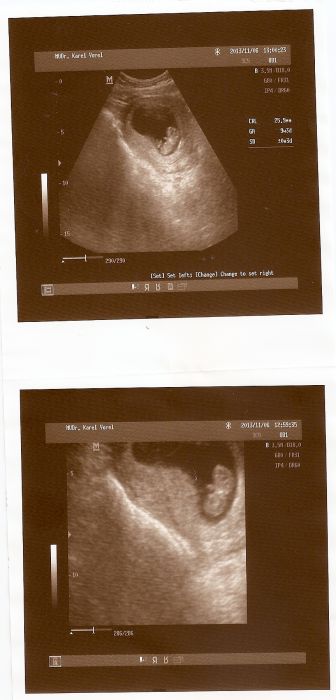

tak posílám fotečky, no řeknite není to holčička

Luci, tvoje miminko je už velký a taky krásný, je úžasný jak už tam jde všechno vidět i nožičky a ručičky,tak ať nám všem rostou